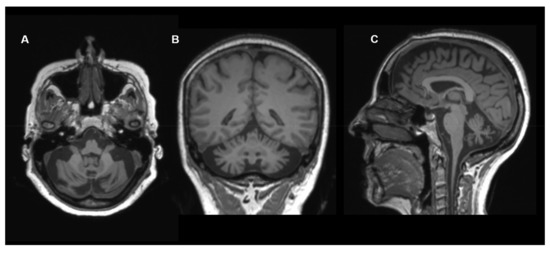

COQ8A encodes for an atypical kinase-like protein relevant for CoQ10 biosynthesis [42,43,44]. Its exact function is still unclear. Disease-causing variants in COQ8A were first described in 2008 (primary coenzyme Q10 deficiency-4; COQ10D4; OMIM #612016) [44]. In 2020, Traschütz et al. published a large cohort of 59 COQ8A individuals, 54 of whom had received brain MRI [45]. They identified cerebellar atrophy as an almost universal finding (94% of patients). Less frequently, cerebral atrophy (8%), stroke-like abnormalities (8%), infratentorial signal abnormalities (4%) and brainstem atrophy (2%) were observed. No structural basal ganglia abnormalities were found. Standardized DTI in three individuals revealed changes of the infratentorial fiber tracts [45]. The findings were consistent with previous reports [44,46]. An example of cerebellar atrophy caused by COQ8A deficiency is depicted in Figure 5.

Figure 5.

Neuroimaging in COQ8A deficiency: Brain MRI (T1-weighted images, (A) axial view; (B) coronal view; (C) sagittal view) of a 60-year-old female with COQ8A deficiency. Images show cerebellar atrophy. Other MRI images of this individual were published previously [45].